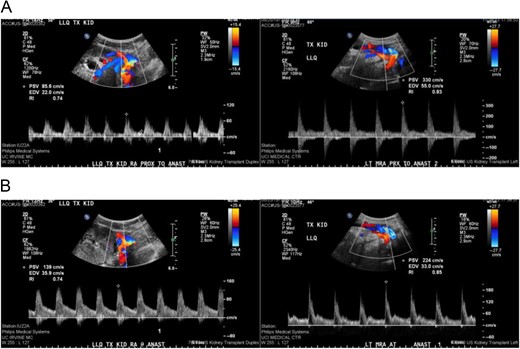

Comparison of duplex ultrasound of transplanted kidney in August 2015 compared to September 2015. Elevated velocities proximal and at the main renal artery anastomosis to 330 cm/s from 85.6 cm proximal to anastomosis (A) and 224 cm/s from 139 cm/s at the site of the anastomosis (B).

Presenting symptoms of nephroptosis most commonly include AKI, abdominal pain, decreased urine output and nausea/vomiting [3]. Doppler studies may reveal elevated flow velocities or complete occlusion of the vascular pedicle, but may also be normal if there is no active torsion of the renal allograft. Most common changes seen in a single study were shown to be reversed arterial diastolic flow, often with vascular thrombosis [1]. Identifying positional variations in renal blood flow may also be useful, although this has not been extensively studied. Sequential CT scans may also demonstrate migration of the renal allograft or change in axis, as was the case described above and has been reported previously as well [4].